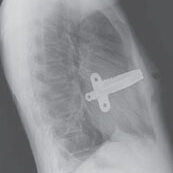

Técnica de Nuss, se usa una barra de metal en forma curvada para que pueda corregir el defecto, el material se retira entre los 18 a 24 meses de la colocación.